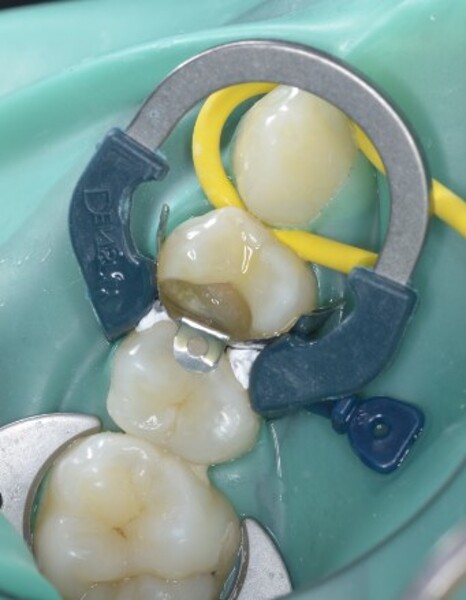

Predictable posterior restorations